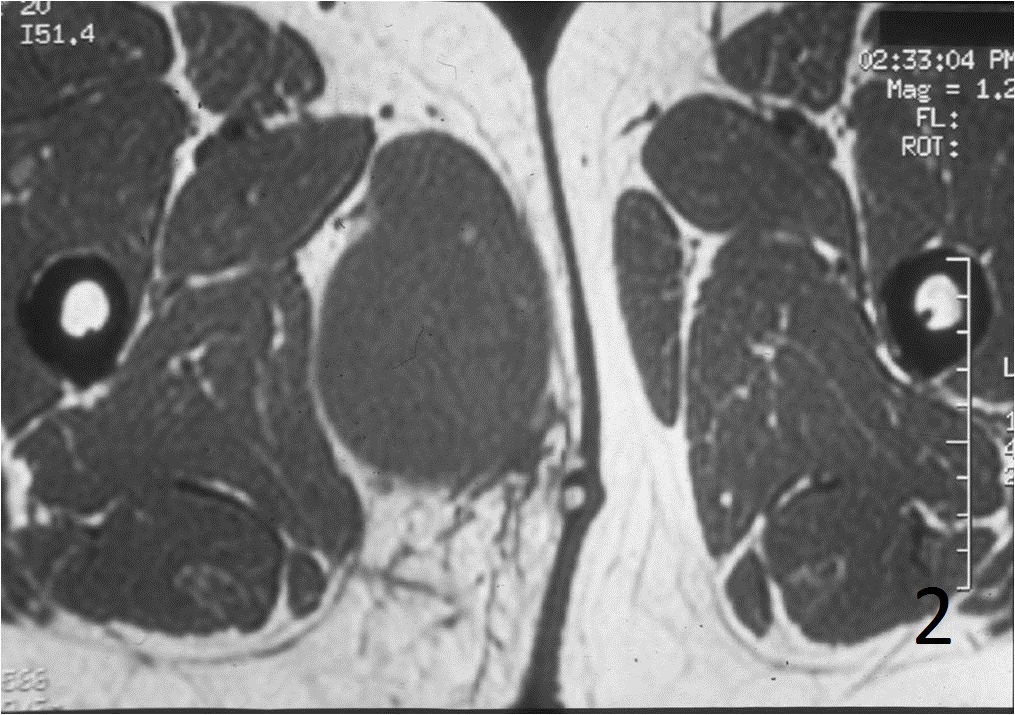

• 60% of fibrosarcomas are intramuscular (Fig. 2, 3, 5, 6, 7, 8)

Fig. 2-4: An MRI of the thigh shows a mass in the medial compartment that is isointense to muscle on T1W images (Fig. 2) and heterogeneous on T2W (Fig. 3). Sagittal T1W post contrast with gadolinium demonstrates enhancement of the tumor (Fig. 4).